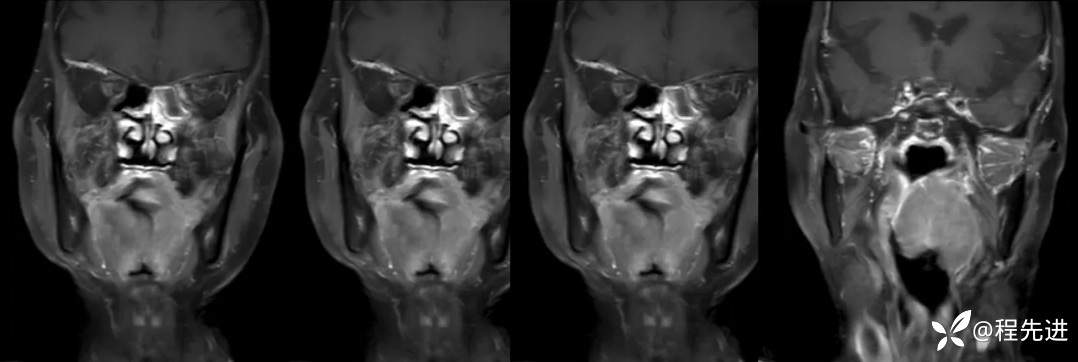

【面颈】特别精彩病例|老年人,反复咽痛1月余,咽部占位期待您的精彩解读!

患者性别:女

患者年龄:78岁

简要病史:反复咽痛1月余

辅助检查:电子鼻咽喉镜:1.咽部新生物性质待定:Ca?淋巴瘤?其他?2.慢性喉炎;3.鼻咽炎

MRI平扫+增强:

T2压脂:

T1压脂增强: